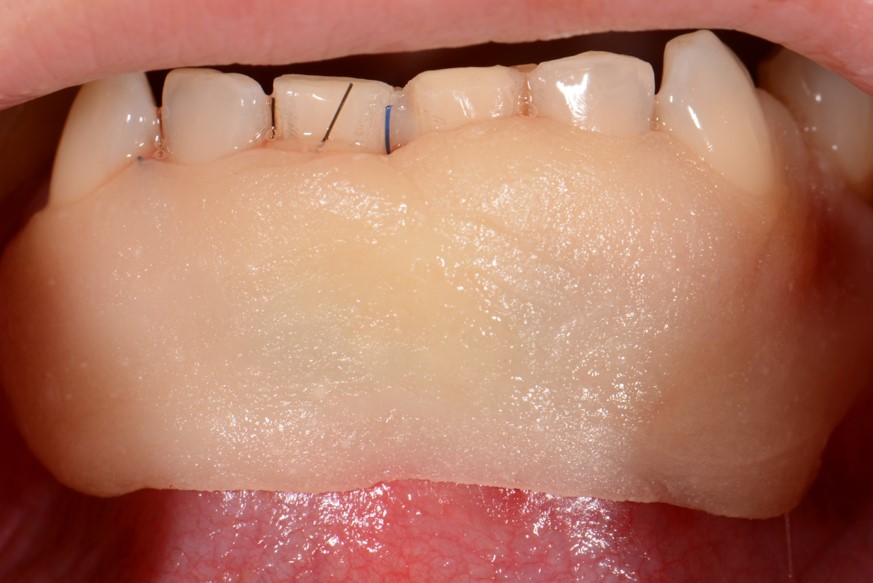

07/12 - Primary wound closure and application of a periodontal dressing.Two-wall intrabony defect treated using cerabone® and Straumann® Emdogain® - Dr. D. Rakasevic & Prof. Dr. S. Jankovic